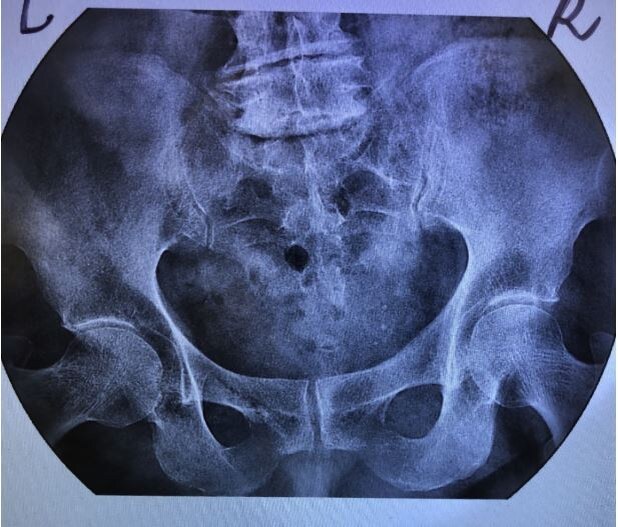

Рис. 1.2. Ренгенография костей таза. На обзорной рентгенографии определяются ассиметричные щели крестцово-подвздошных сочленений (неравномерное сужение справа, приманки субхондрального склероза). Щели тазобедренных суставов сужены, умеренный субхондральный склероз замыкательной пластинки вертлужной впадины с обеих сторон. Рентгенографические признаки двустороннего коксартроза 2 ст., правостороннего сакроилеита 1-2 ст. (Изображение из личного архива, разрешено к публикации).